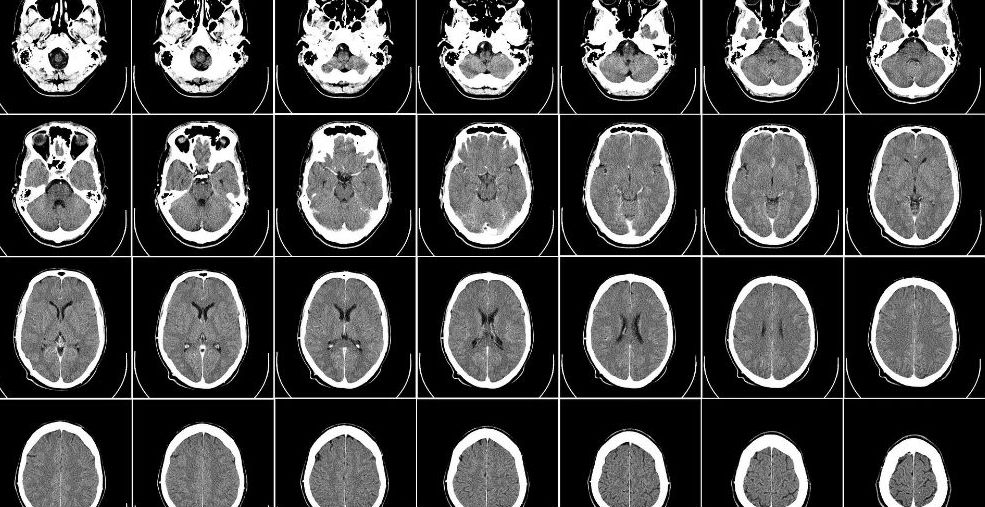

Coverys, an insurance provider to physicians, last year released a report on medical malpractice claims involving radiologists titled, “Claims Data Signals & Solutions to Reduce Risks and Improve Patient Safety.” A radiologist is a medical doctor who uses a variety of electronic testing – such as x-rays and MRIs – to diagnose and treat patients. A radiologist often consults another physician following a referral for clinical testing.

The most frequent basis for a medical malpractice lawsuit against a radiologist involved a patient’s misdiagnosis. Radiologists were involved in 15 percent of misdiagnosis medical malpractice lawsuits, second behind only general medicine physicians. And 80 percent of those medical malpractice claims in the study involved a misinterpretation of a clinical test by a radiologist.